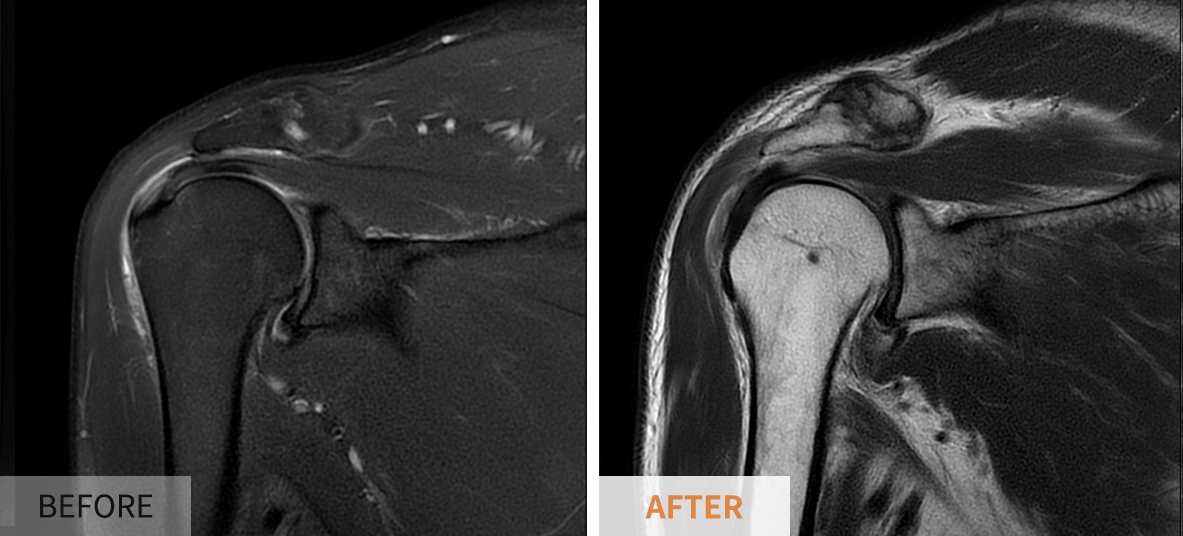

신체 검사 결과에 따라 추가적인 영상 검사가 필요할 수 있습니다. 일반적으로 사용되는 검사 방법에는 ▶️ X-레이, ▶️ 초음파, ▶️ MRI 등이 있습니다. X-레이는 뼈의 상태를 확인하는 데 도움을 주고, 초음파는 연조직의 구조와 상태를 파악하는 데 유용합니다. MRI는 보다 상세하게 손상의 정도를 평가할 수 있어 회전근개 파열 진단에서 특히 유용합니다.